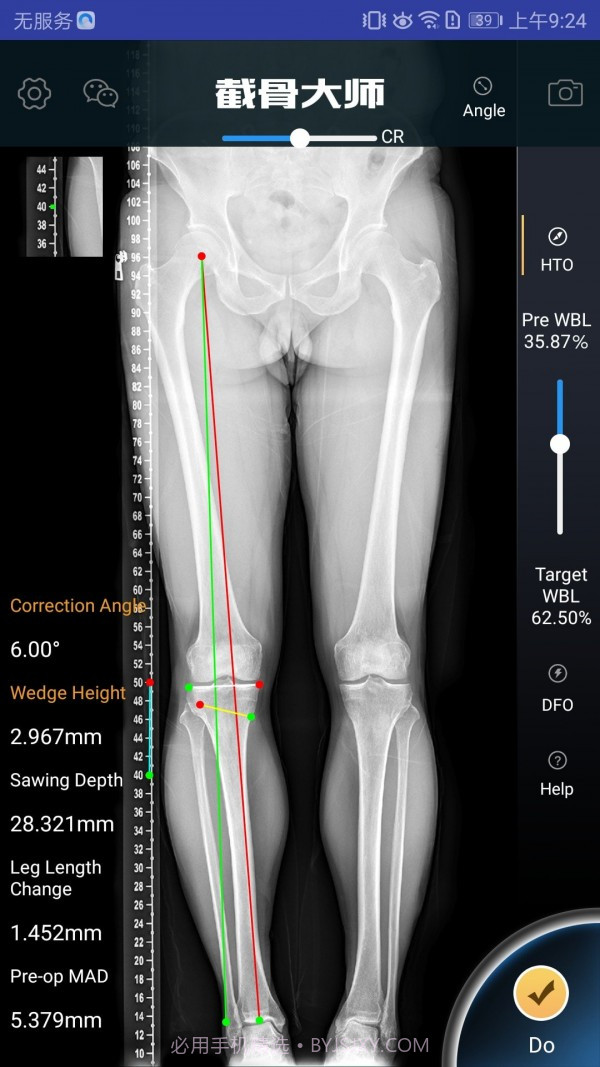

截骨大师真的是个宝藏APP,特别适合骨科医生和医疗人员使用。此外,它的手术模拟能力超级高效,能让医生在手术前清晰地了解手术效果,避免在实际操作中出现失误。而且,它的参数计算非常精准,真的是为医生的工作提供了很大的帮助。用这款软件,你不仅能节省大量准备时间,还能显著提高手术的成功率,对患者的治疗也有很大保障。作为医生,这款工具简直是必不可少的选择。

软件截图